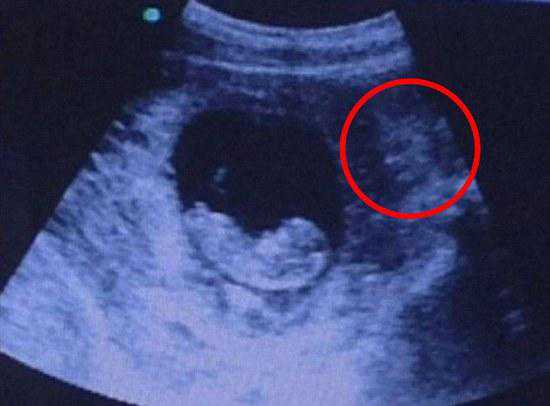

原来这张超声波照片,看上去有一只酷似猫的东西正注视着子宫内的胎儿,这就让人毛骨悚然了,一下子联想到古代“狸猫换太子”的说法,虽然没什么科学依据,但老人家觉得这个孩子不吉利、要不得,硬是要章女士打掉孩子,章女士觉得这纯属无稽之谈,自己好不容易怀上的宝宝哪能说不要就不要!

幸孕姐解说:首先根本不存在“狸猫换太子”一说,章女士的婆婆固然有些封建迷信思想,既然医生都说超声波检测胎儿发育正常,那就没问题,其实这些都是人们根据视觉感官臆想出来的东西。

从医学角度看,宝宝处在不断发育和运动中,宝宝周围的胎盘组织(羊膜、叶状绒毛膜和底蜕膜)会随着胎儿的运动发生位置改变,在加上拍照角度的影响,所以才会拍出恐怖的象形化胎儿照片。为此幸孕姐特意收集了以下会让父母心情一下从天堂掉到地狱的恐怖超声波照——